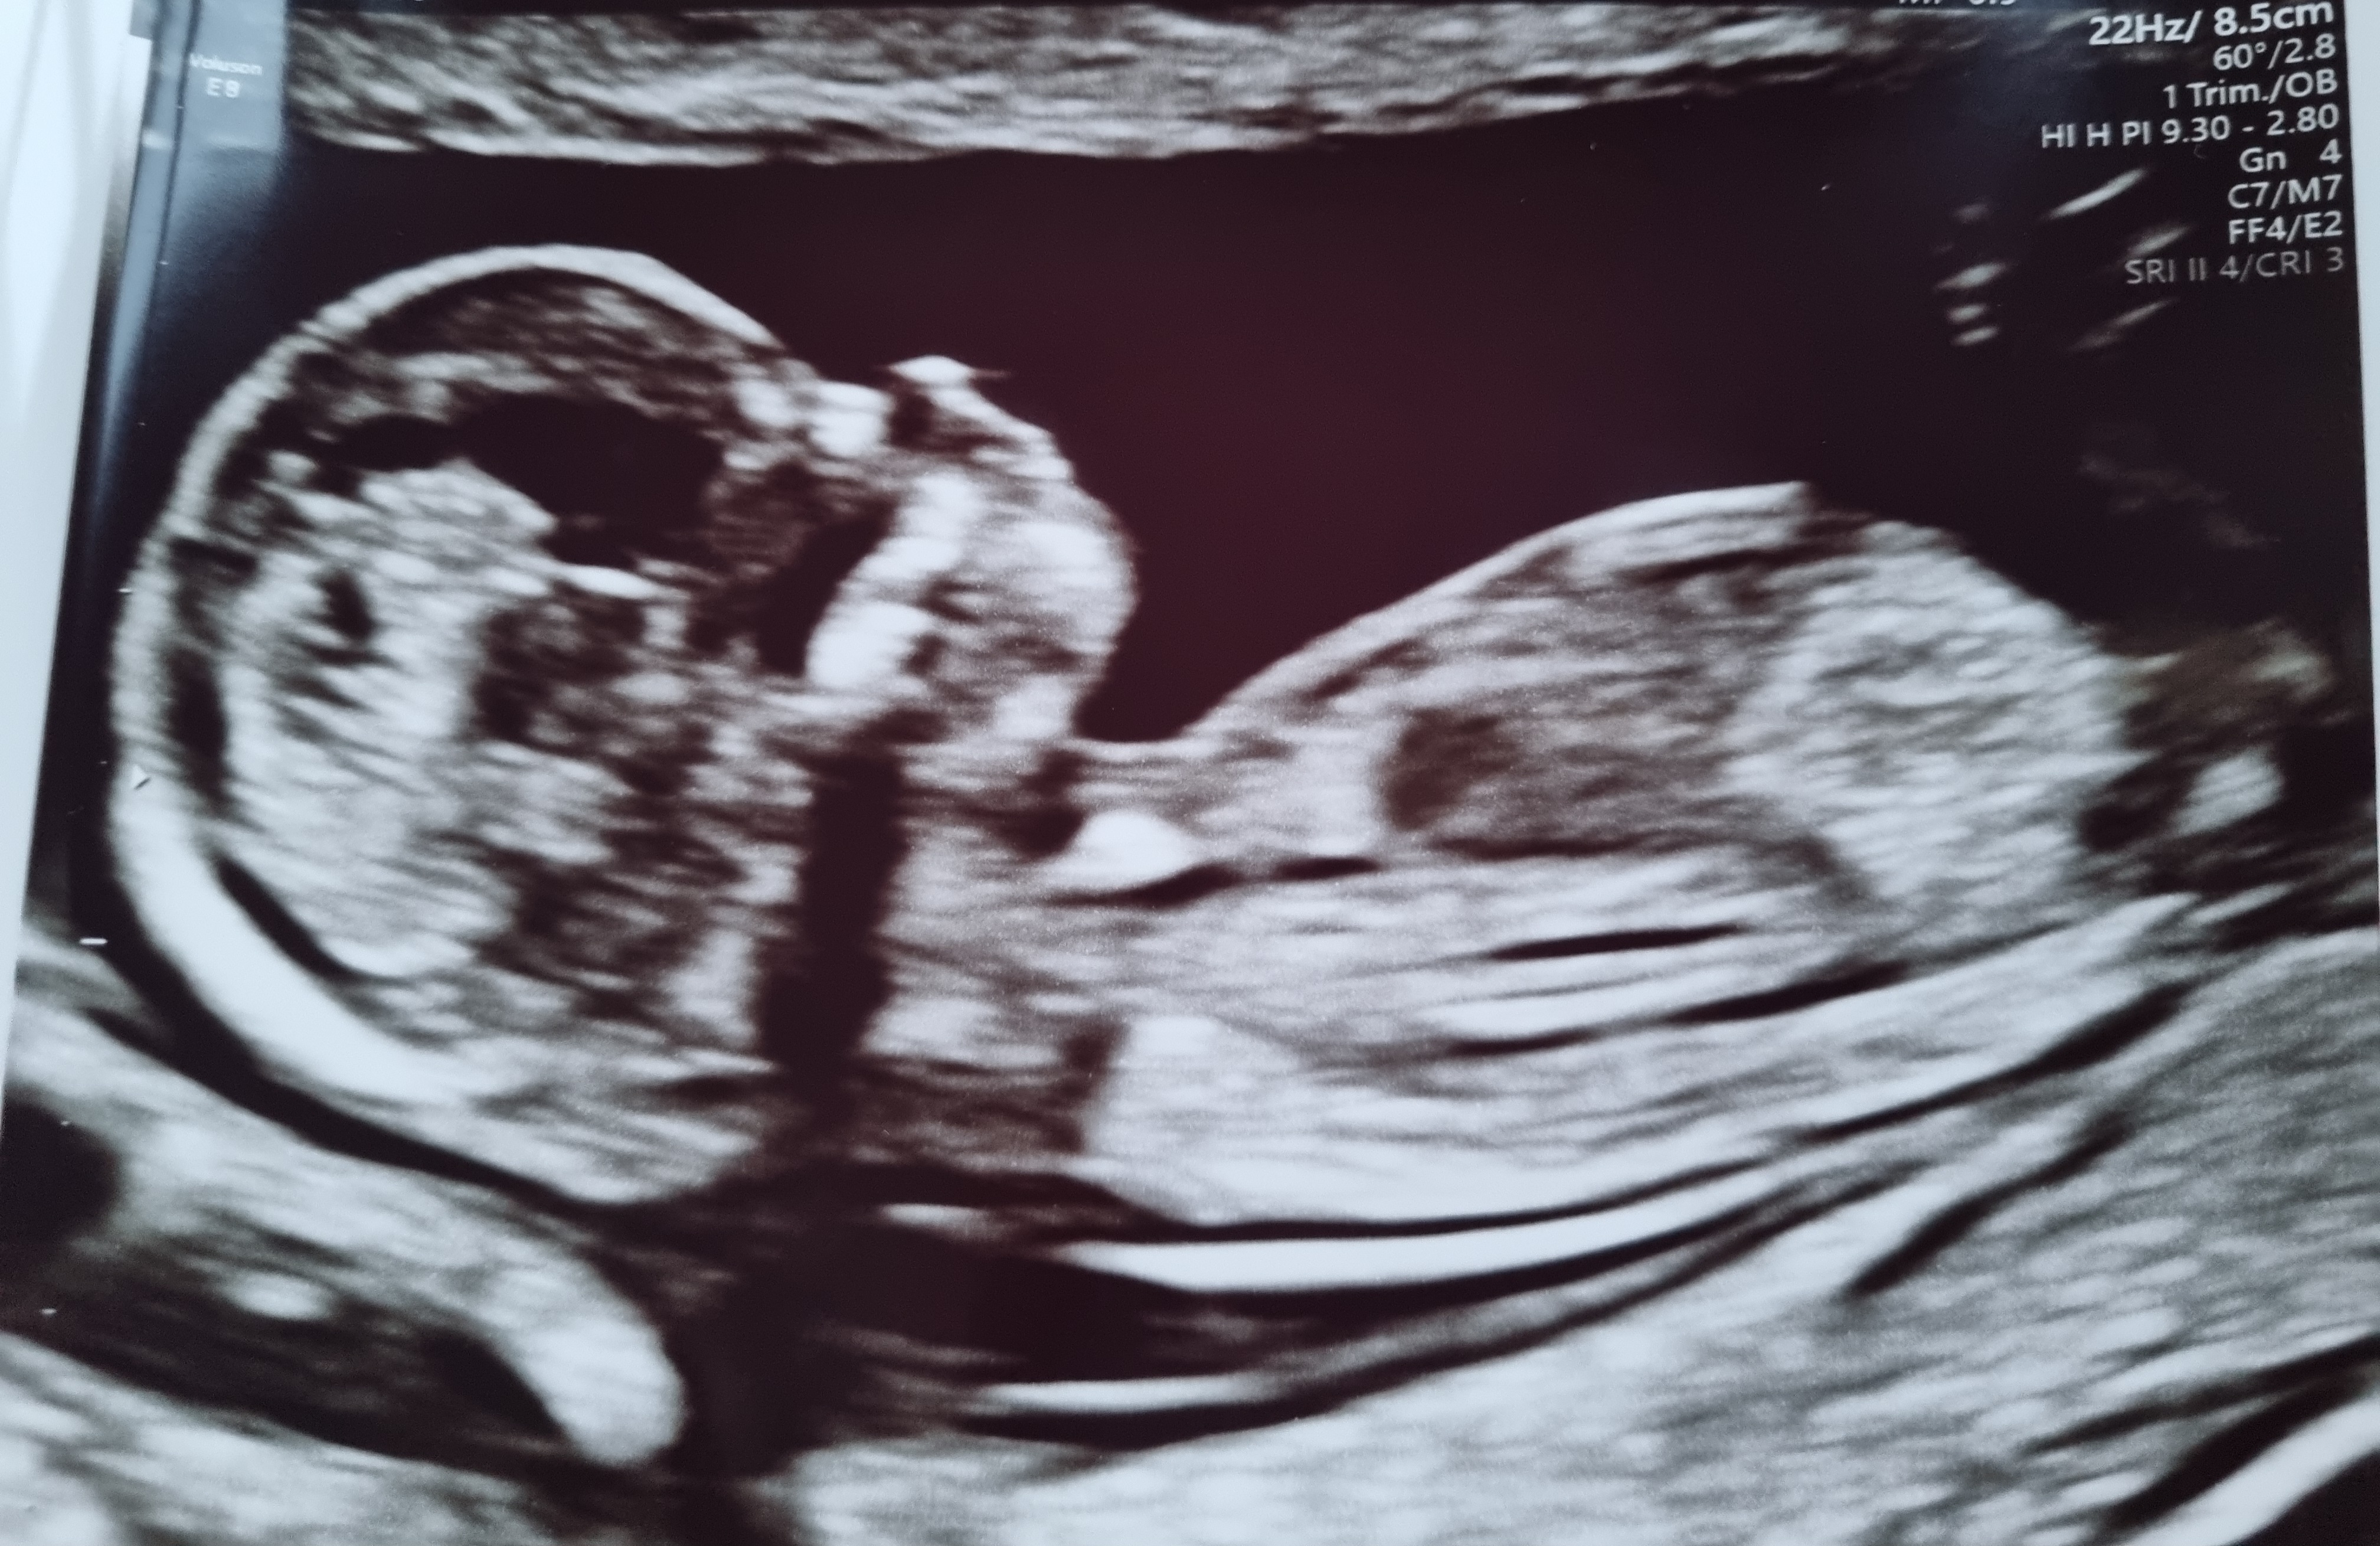

12+3 (målt til 12+5 idag)

Vi har en bebis perfektus på vei! Alt så helt perfekt ut, Lille var veldig aktiv, vinket, sprellet, strakk seg ut. Legen kalte den skihopper

Jeg kunne sett på den i evigheter, og vi fikk med oss ni bilder! Nå er alt verdt det. All kvalme, all smerte, all bekymring, alt er blåst vekk! Fin nakkefold, fin nese, ti små fingre, perfekte små armer og bein

Syns det er så rart å tenke på når man er på OTUL, at selve fosteret er kanskje rundt 8-10 cm - og på skjermen ser det ut som en ferdig baby. Trenger bare å vokse seg stor og sterk!